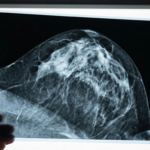

Episode 10.5 The Dense Breast Dilemma

Howard and Antonia explore the safety of medications during pregnancy and the controversial reporting requirements for breast density on mammograms, examining how science is being overshadowed by fear-mongering in healthcare […]